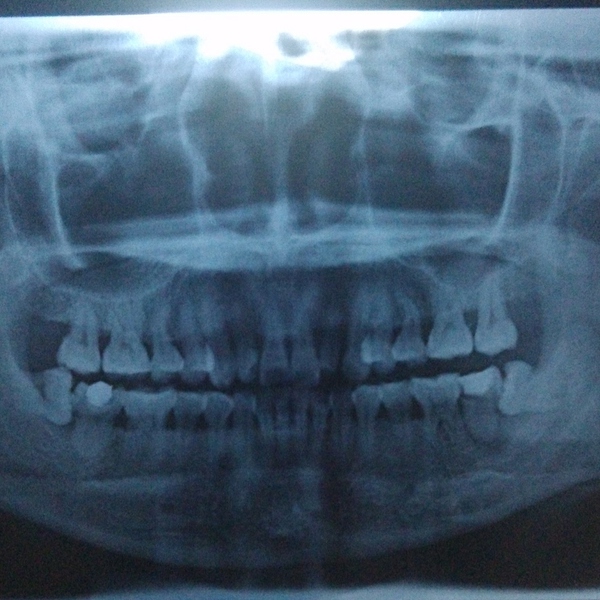

牙齿萌出困难称为"阻生齿"或"埋伏牙"。阻生齿最常见于下颌第三磨牙,俗称智齿,此牙萌出年龄在18岁前后,由于萌出前其它牙齿都早已站好队列了,等智齿生长出来时,就会受到其它牙齿的排挤,故而萌出困难,形成了阻生齿或埋伏牙,我们称之为"阻生智齿"。

首先并不是每个人都有机会萌出全部四颗智齿,如果某一颗没有对生的,有可能会造成对位的口腔黏膜磨损,多见于下位。 其次,阻生智齿一定要拔除。阻生简而言之就是你的口腔骨骼没有给那颗牙留足够的位置,这样智齿就会用把兄弟姐妹往旁边挤的粗暴方式长出来。这个过程中,任何的外界刺激,食物残渣残留都可能造成严重感染,

这种情况下就一定要先消炎然后拔除。否则以后你每次发烧感冒都可能使智齿感染,反过来也一样。 一般来说阻生智齿拔除不是大手术,上牙比下牙好拔除,但依据你的牙齿状况,过程可能持续10到15分钟,一定会打麻药,麻药负责你那半边脸的痛感缺失。手术过程中首先要划开牙龈,然后非常可能用到锤子和其他工具把牙撬出,或如果你的牙形比较细长,可能直接敲碎拿镊子夹出。手术风险:如果你的牙根非常长,长到和其下的神经有粘连,可能导致局部的永久性麻痹。术后:每个医生都会告诉你多久拿掉填充物多久可以刷牙。